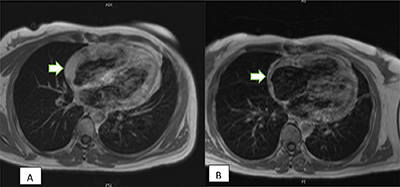

本文讨论了原发性心脏肿瘤的罕见性,尤其是血管肉瘤,占原发性心脏肿瘤的 10%。文章强调了非特异性症状给早期诊断带来的挑战。文章强调了切面成像,尤其是计算机断层扫描(CT)在紧急情况下的重要性。教学要点:尽管原发性心脏肿瘤非常罕见,但放射科医生仍应保持警惕,尤其是出现心包积液时。

This article discusses the rarity of primary cardiac tumors, particularly angiosarcomas, accounting for 10% of primary cardiac neoplasms. The article highlights the challenge of early diagnosis due to nonspecific symptoms. The importance of sectional imaging, particularly computed tomography (CT) scans, in emergent situations is emphasized. Teaching point: Despite the rarity of primary cardiac tumors, radiologists should remain alert, especially when pericardial effusion is present.